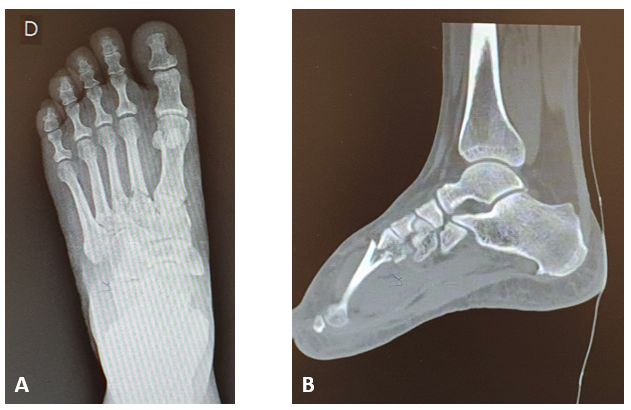

Female patient, forty-four years old, domestic, no comorbidities, sought care in an Emergency Care Unit, due to blunt trauma on right foot (five kilograms object drop), after approximately 2 hours. On orthopedic physical examination, she presented edema (3+/4+) and significant pain on dorsum of right foot, without neurovascular injuries. The radiograph and computed tomography of the foot showed fractures at the base of the 2º, 3º and 4º metatarsal, with no joint damage (Figures 1A & 1B).

Figure 1 Radiograph (A) and computed tomography imaging (B) of the foot indicating fracture at the base of the 2º, 3º and 4º metatarsal. Source: Author’s personal arquive.

To perform the procedure, the patient underwent spinal anesthesia. After that, the fasciotomy occurred through two dorsal incisions (lateral and medial) (Figure 2A). At this point, to reduce additional damage of soft tissues, the mechanic stabilization of the fractures was performed through Kirschner wires 1.5mm, which was placed transversely (Figure 2B).

Figure 2 Clinical (A) and radiograph imaging (B) in the immediate postoperative of fasciotomy and osteosynthesis of the foot fractures. Source: Author’s personal arquive.